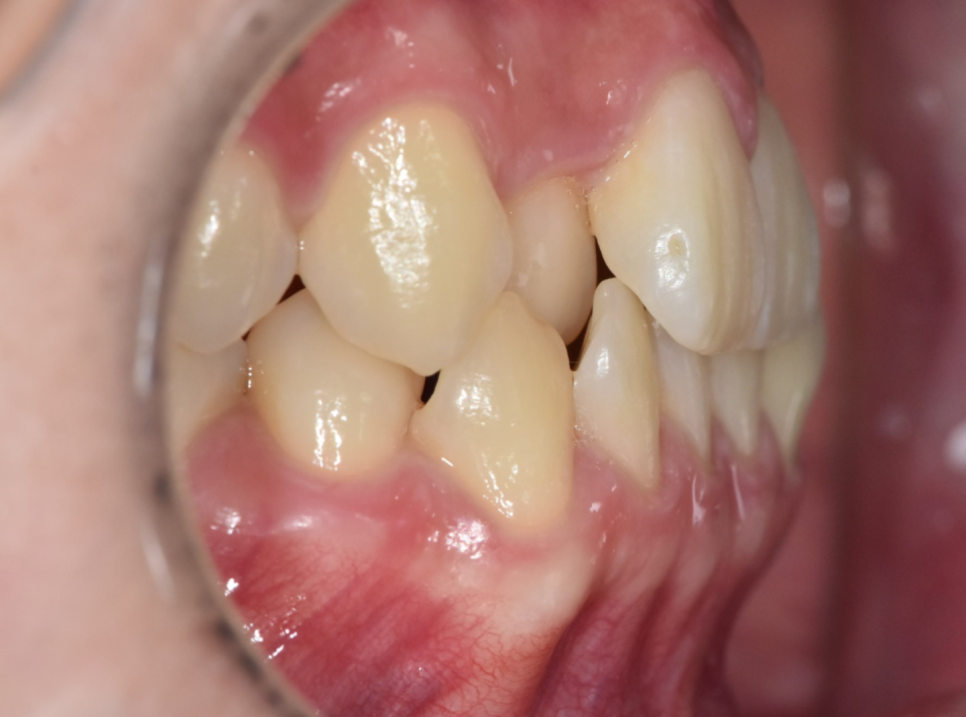

사진처럼 다른 치아에 비하여 안쪽으로 들어가 있기도 하고

튀어 나와있는 경우도 있지만

치아 배열이 울퉁불퉁한 것이라 보시면 됩니다.

250616 양치가 어렵겠죠?

들어가 있는 치아와 나와있는 치아

불규칙한 치아 배열로 칫솔질이 어렵고

양치가 잘 안되는 사각지대가 생길 수 있겠죠??

충치·잇몸질환 위험이 증가할 수 있고

교합이 맞지 않아 턱관절에 무리가 가해질 수 있습니다.